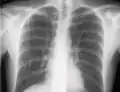

If a pneumothorax is suspected, an upright chest x-ray should be obtained. An upright chest x-ray is preferred because free air will migrate to the apex of the lung, where it is easily visualized. Of course, this is not always possible, particularly in critically ill patients in the intensive care unit. Radiographs obtained in the supine position fail to detect 25–50% of pneumothoraces.[6] Instead, bedside ultrasound is a superior method of detection in those too ill to obtain upright imaging.[3]

During subclavian vein central line placement, the catheter can be accidentally pushed into the internal jugular vein on the same side instead of the superior vena cava. A chest x-ray is performed after insertion to rule out this possibility.[26] The tip of the catheter can also be misdirected into the contralateral (opposite side) subclavian vein in the neck, rather than into the superior vena cava.

The line is then inserted using the Seldinger technique: a blunt guidewire is passed through the needle, then the needle is removed. A dilating device may be passed over the guidewire to expand the tract. Finally, the central line itself is then passed over the guidewire, which is then removed. All the lumens of the line are aspirated (to ensure that they are all positioned inside the vein) and flushed with either saline or heparin.[1] A chest X-ray may be performed afterwards to confirm that the line is positioned inside the superior vena cava and no pneumothorax was caused inadvertently. On anteroposterior X-rays, a catheter tip between 55 and 29 mm below the level of the carina is regarded as acceptable placement.[37] Electromagnetic tracking can be used to verify tip placement and provide guidance during insertion, obviating the need for the X-ray afterwards.

Chest x-ray with catheter in the right subclavian vein -

The outline of superior vena cava on a chest X-ray is labeled at left.